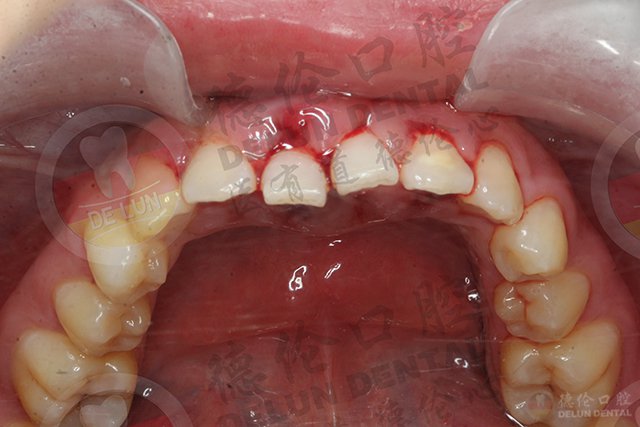

口腔异味、牙龈红肿出血、牙齿松动……千万别小瞧了这些生活中常见的口腔问题,可能是牙周病的发病症状!

牙周是指:覆盖在牙根上的牙周韧带、牙槽骨、牙骨质以及外层的牙龈。牙周就像地基,将牙齿紧密地固定在颚骨内,牙齿才能用力咀嚼食物。牙周病就是发生在牙周地方的各种疾病,包括牙龈病和牙周炎。牙周病是我们口腔的常见病、多发病,也是成年人牙齿脱落的主要原因。